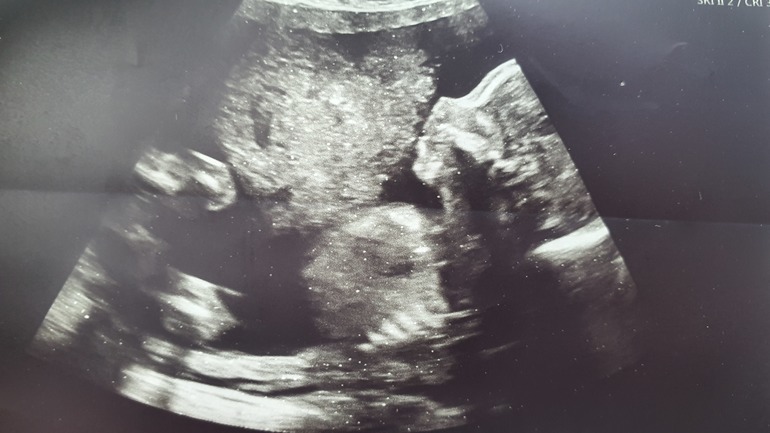

Что касается самочувствия, да, годы дают своё, я уже не та шустрая девчонка, которая даже на роды ехала сама за рулём. Я старая больная обезьяна)))) устаю быстро, стала медлительная, тупенькая, забывчивая. С утра сама уже не могу на коляску с кровати пересесть, в машину еле пересаживаюсь, на пандусы не могу сама заезжать. Веса набралось много, + 12 уже, сказалось, что резко бросила спорт и диету кетоновую. Но вес и слабость меня не пугают, я знаю, что форму я верну, главное наша малышка растёт и всё у нас хорошо, все показатели в норме. И вся семья её очень любит и ждёт. И да, все уже решили, что её зовут Виктория. И фото нашей малышки: